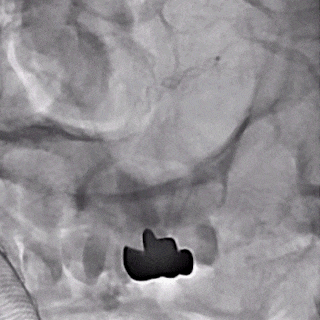

支架及支架微导管到位。

支架头端打开。

支架远端打开造影。

等张释放,支架中段打开至50%释放标记点。

支架中段打开造影。

支架近端打开,完全释放。

支架完全释放造影。

术后即刻造影。